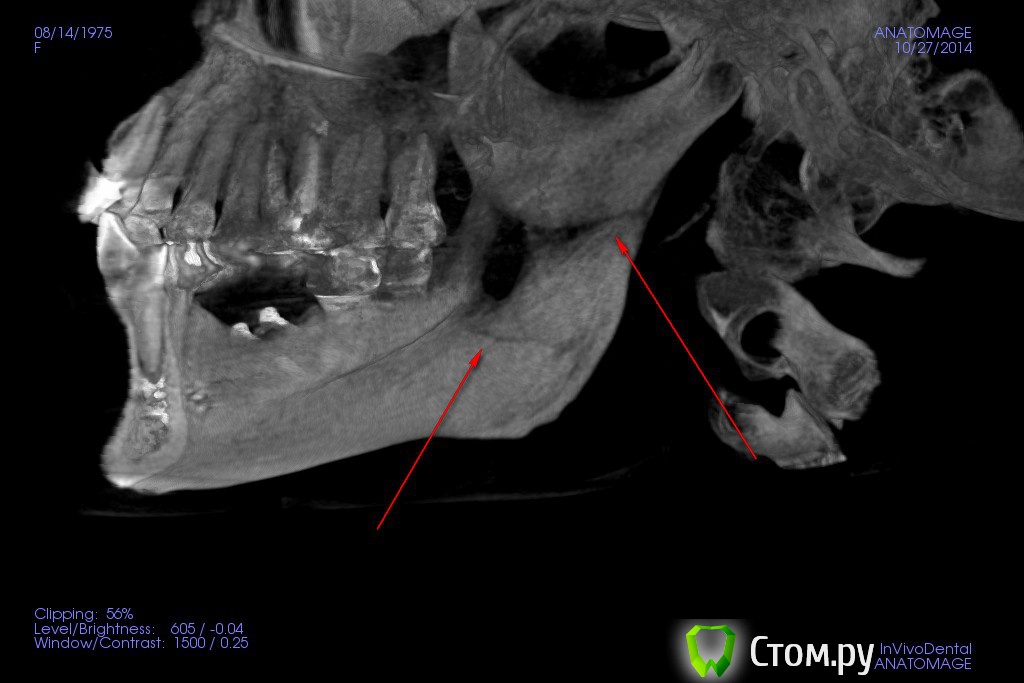

Марьяна Опубликовано 22 ноября, 2014 Поделиться Опубликовано 22 ноября, 2014 (изменено) Уважаемые врачи. У меня возникло некое недопонимание с достаточно уважаемым коллегой.По данным КТ я вижу двойной перелом ветви челюсти. Он мне говорит, что это артефакты. И советует сделать спиральную томографию и для него КЛКТ не информативна.Прилагаю 3D реформат, до и спустя 4 месяца после операции аугментации с забором костного блока ретромолярно на нижней челюсти справа. Сразу отмечу- это моё КТ. Пациентом являюсь я сама.Если необходимо будет, вышлю дайкомы. Первый файл до операции. Остальные после. Первые два - программа EZ-Vision. Если понизить плотность костной ткани(в программе естественно), то будет видно, что был так же перелом в области угла. Два файла последних - программа Invivo5(Анатомаж).Нужны ваши мнения. Изменено 22 ноября, 2014 пользователем Марьяна Ссылка на комментарий

Марьяна Опубликовано 22 ноября, 2014 Автор Поделиться Опубликовано 22 ноября, 2014 Попробую. В программе конечно проще поймать линии переломов.Ну вот ..в области конкретно ветви: Ссылка на комментарий

Марьяна Опубликовано 22 ноября, 2014 Автор Поделиться Опубликовано 22 ноября, 2014 В области угла зигзагообразная линия ..практически уже не визуализируется: Ссылка на комментарий

Марьяна Опубликовано 23 ноября, 2014 Автор Поделиться Опубликовано 23 ноября, 2014 (изменено) Если и был перелом, то без смещения и уже зажил...отправьте дайкомы Дмитрию Рогацкину.Да, зажил, и слава Богу. Отправлять дайкомы Рогацкину смысла нет. Он скажет, то, что есть. А есть двойной перелом. Я сама есть консультант по 3D КТ, :-) С Иваном Морозовым , который представляет Рогацкина у нас в Новосибе мы уже пообщались и в Анатомаже он и сделал мне одну из нарезок. И рентгенолог, которго хвалит Рогацкин, тоже в курсе)Смещение , кстати, есть, небольшое, дистально.Это видно по дистальному контуру ветви.Почему я выношу на общее обсуждение свою историю? Ну мне обидно, да. Обидно, что со мной так обошлись коллеги. Что по необъективным причинам, без уведомления был изменен план лечения. Что скрыли истинную причину, по которой срочно прекратили операцию и отложили вторую на две недели. Позиция лечащего врача сейчас убивает наповал. Я даже по-началу засомневалась в своей компетентности, увидев повторное КТ и его резюме по нему.Я ещё хотела написать вот что. Суть моего поста здесь. По факту..я имею право предьявить претензию, но не хочу. Слава Богу, что все обошлось без серьезных осложнений. Что не было остеомиелита, что не случилось явного смещения, несмотря на то, что перелом не был шинирован и т.д. и .т.п.Я оскорблена поведением врача. У нас у всех есть свое маленькое кладбище и мы знаем и помним о всех своих ошибках. Но надо уметь признавать ошибки и исправлять. И если именитый врач ведет себя, как нашкодивший пацан...если между коллегами такое вот отношение, страшно за пациентов, которые вообще не в теме.В общем...лозунг какой-то получился) Уважайте своих пациентов и друг друга. Изменено 23 ноября, 2014 пользователем Марьяна 5 Ссылка на комментарий

Bier Опубликовано 23 ноября, 2014 Поделиться Опубликовано 23 ноября, 2014 Да, зажил, и слава Богу. Отправлять дайкомы Рогацкину смысла нет. Он скажет, то, что есть. А есть двойной перелом. Я сама есть консультант по 3D КТ, :-) С Иваном Морозовым , который представляет Рогацкина у нас в Новосибе мы уже пообщались и в Анатомаже он и сделал мне одну из нарезок. И рентгенолог, которго хвалит Рогацкин, тоже в курсе)Смещение , кстати, есть, небольшое, дистально.Это видно по дистальному контуру ветви.Почему я выношу на общее обсуждение свою историю? Ну мне обидно, да. Обидно, что со мной так обошлись коллеги. Что по необъективным причинам, без уведомления был изменен план лечения. Что скрыли истинную причину, по которой срочно прекратили операцию и отложили вторую на две недели. Позиция лечащего врача сейчас убивает наповал. Я даже по-началу засомневалась в своей компетентности, увидев повторное КТ и его резюме по нему.Я ещё хотела написать вот что. Суть моего поста здесь. По факту..я имею право предьявить претензию, но не хочу. Слава Богу, что все обошлось без серьезных осложнений. Что не было остеомиелита, что не случилось явного смещения, несмотря на то, что перелом не был шинирован и т.д. и .т.п.Я оскорблена поведением врача. У нас у всех есть свое маленькое кладбище и мы знаем и помним о всех своих ошибках. Но надо уметь признавать ошибки и исправлять. И если именитый врач ведет себя, как нашкодивший пацан...если между коллегами такое вот отношение, страшно за пациентов, которые вообще не в теме.В общем...лозунг какой-то получился) Уважайте своих пациентов и друг друга.а как бы он зажил без шинирования? Т.е. врач увидел, что сломал челюсть, закончил операцию, не шинировал и челюсть сама собой зажила? Это все маловероятно. Скорее всего перелома не было, может быть трещина, которая осталась недиагностированной. Ссылка на комментарий